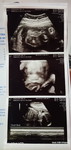

ano po ang pwede inomin masama po pakiramdam ko 6months pregnant

6month pregnant